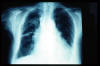

Fibrosis pulmonar. ICC.